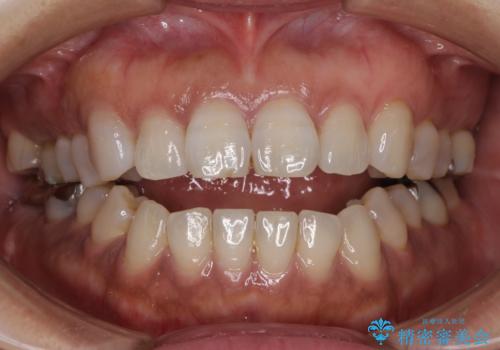

極端な上下前歯の開咬を改善 オープンバイトのインビザライン矯正

治療前に、いくらインビザライン矯正がオープンバイトを得意としているとは言え、さすがに限界があるだろうと思っておりましたが、前歯でレタスが噛めるまで改善することができました。

顔の印象も大きく変わり、患者様には大変満足していただきました。